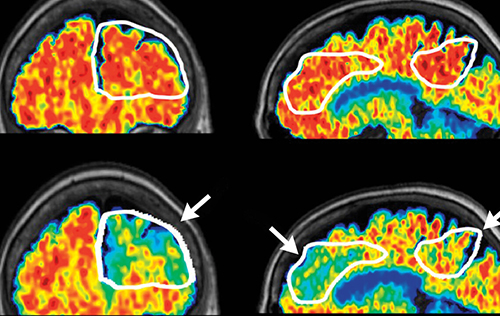

brain scan imaging in red, yellow, blue, and green